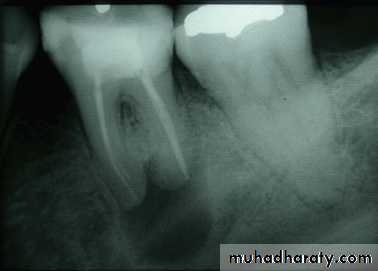

Periapical lesion associated with endodotically treated canals

Regression of the lesion 6 months after retreatment of the tooth